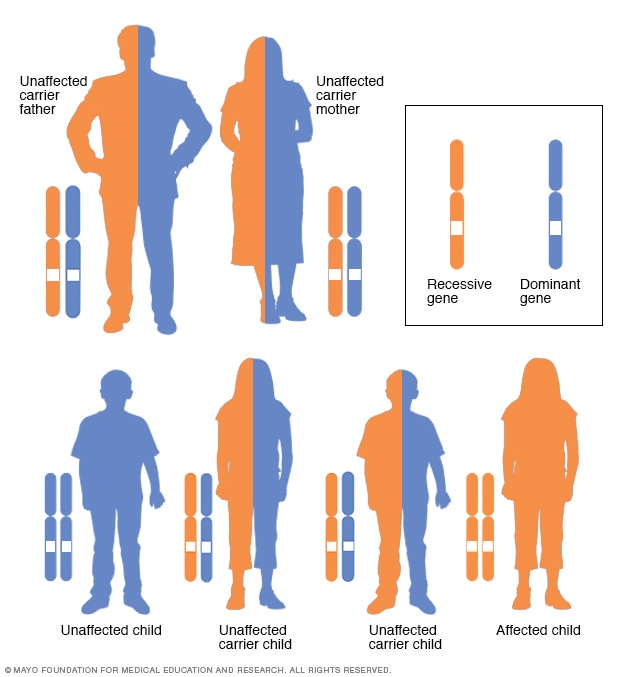

Autosomal recessive inheritance pattern

To have an autosomal recessive disorder, you inherit two changed genes, sometimes called mutations. You get one from each parent. Their health is rarely affected because they have only one changed gene. Two carriers have a 25% chance of having an unaffected child with two unaffected genes. They have a 50% chance of having an unaffected child who also is a carrier. They have a 25% chance of having an affected child with two changed genes.

In cystic fibrosis, a change in a gene causes problems with the protein that controls the movement of salt and water in and out of cells. This gene is the cystic fibrosis transmembrane conductance regulator (CFTR) gene. It affects the cells that make mucus, sweat and digestive juices. When the CFTR protein doesn't work as it should, the result is thick, sticky mucus in the respiratory, digestive and reproductive systems, as well as extra salt in sweat.

Changes in the CFTR gene that cause CF are divided into several different groups based on the problems they cause. Different groups of gene changes affect how much CFTR protein is made and how well it works.

To have cystic fibrosis, children must get one copy of the changed CFTR gene from each parent. If children get only one copy, they won't develop CF. But they will be carriers and could pass the changed gene to their own children. People who are carriers may have no symptoms of CF or a few mild symptoms.